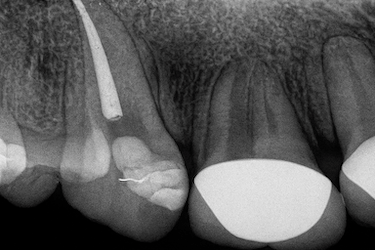

Se realizan pruebas de sensibilidad y una radiografía periapical o panorámica para confirmar si existe daño pulpar o inflamación en la raíz. Estas imágenes ayudan a planificar el tratamiento de conducto con precisión.

El sellado, o obturación, se realiza con precisión para confirmar que el relleno cubre toda la raíz y queda perfectamente aislado.

Antes de finalizar, el odontólogo realiza una radiografía de control para confirmar que el sellado está correcto y que no hay signos de infección.